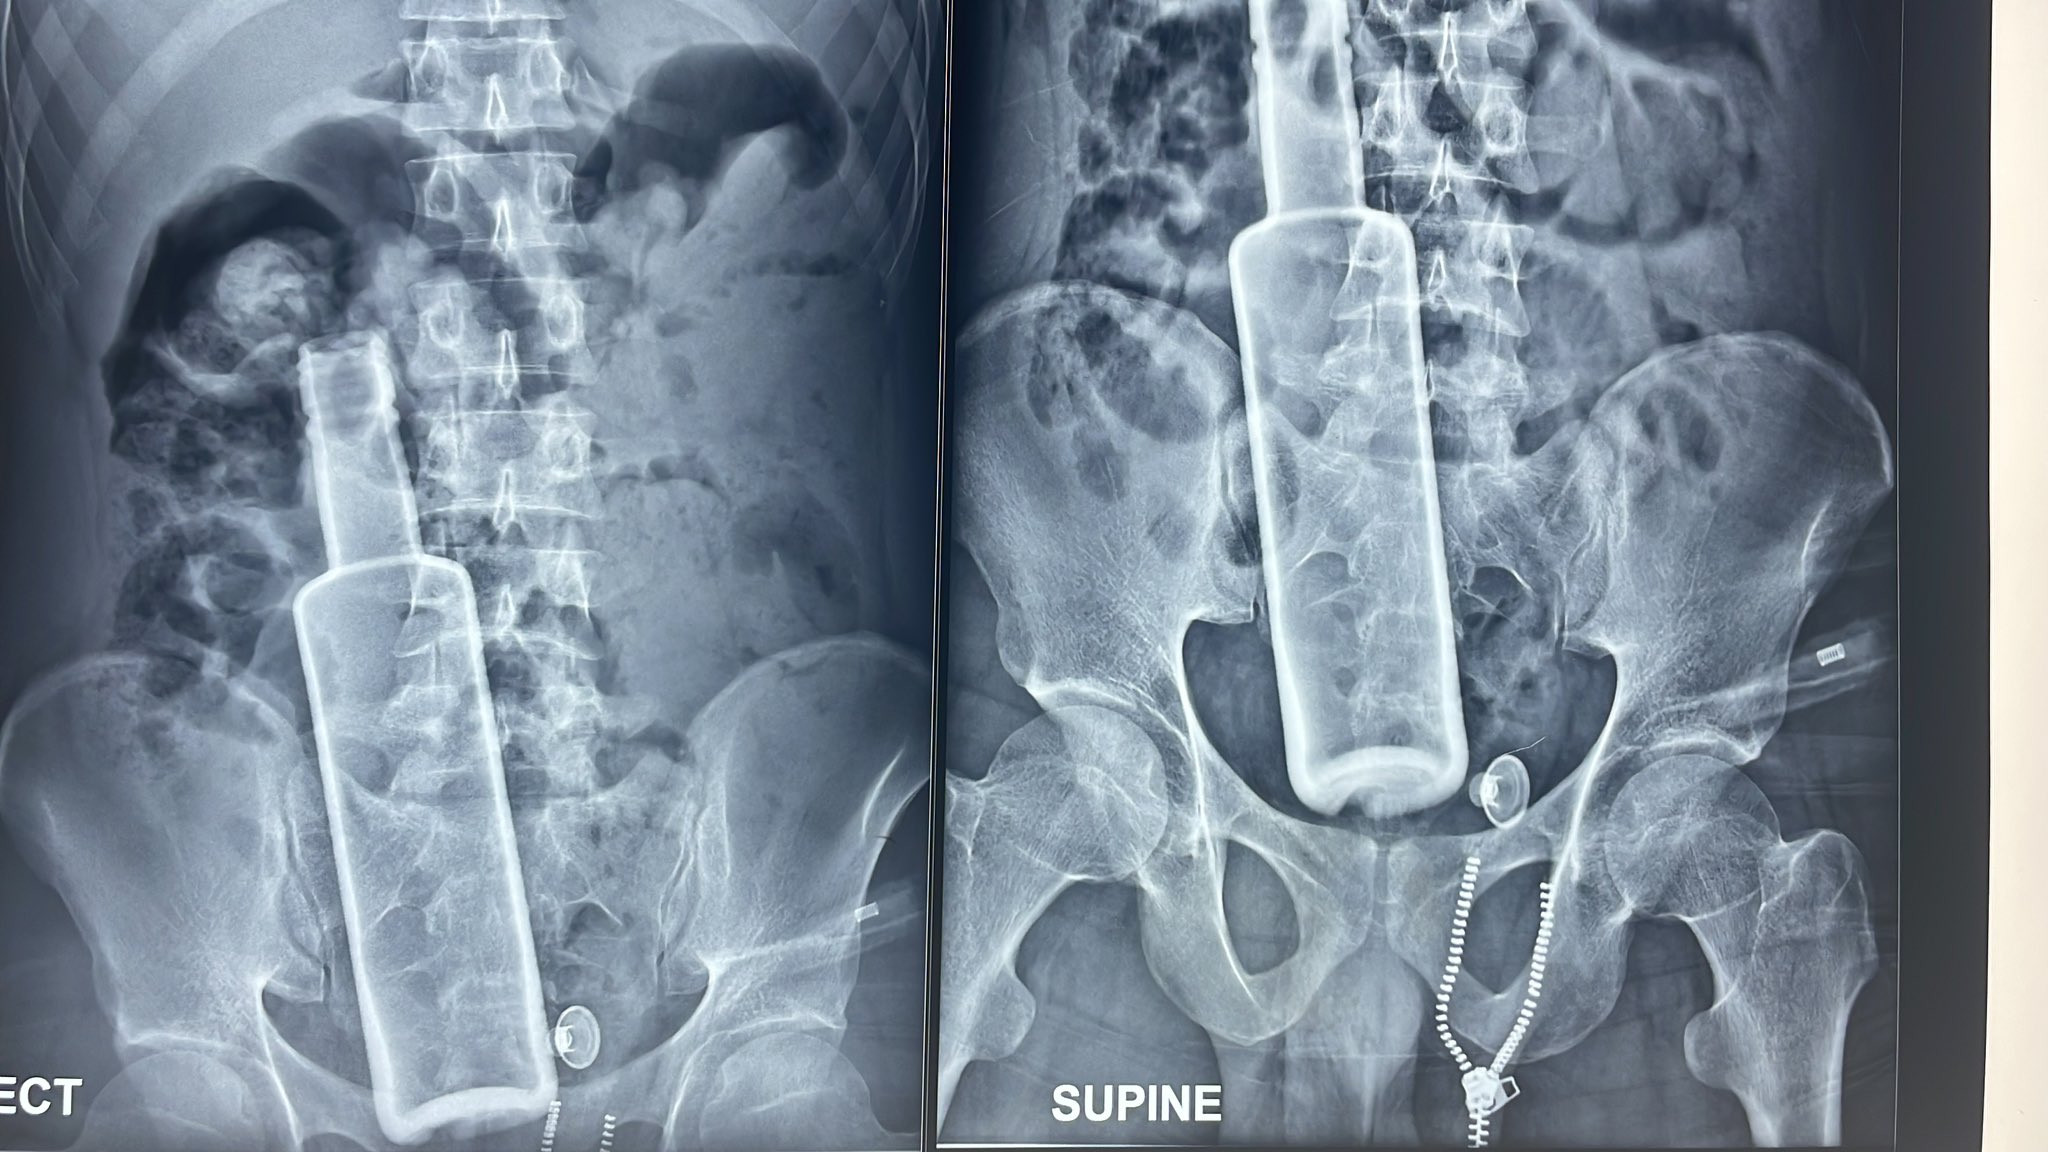

बिरामीको पेटभित्र भेटियो रक्सीको सिंगै बोतल !

भरतपुरस्थित पुरानो मेडिकल कलेज शिक्षण अस्पतालको आकस्मिक कक्षमा केही व्यक्तिले एक गम्भीर अवस्थाका बिरामी ल्याइपुर्‍याए। रौतहटको चन्द्रनिगाहपुरबाट ल्याइएका बिरामीको नाडीको चाल १२० भन्दा माथि पुगेको थियो। पेट फुलेर ठूलो भएको थियो। बिरामीसँग आएका व्यक्तिको साथमा रहेको एक्सरे रिपोर्ट डाक्टरलाई नै तर्साउने खालको थियो। एक्सरेमा उनको पेटमा एउटा सिंगो बोतल देखिन्थ्यो। ‘पेटमा बोतल छ भन्ने उताको एक्सरेबाट […]